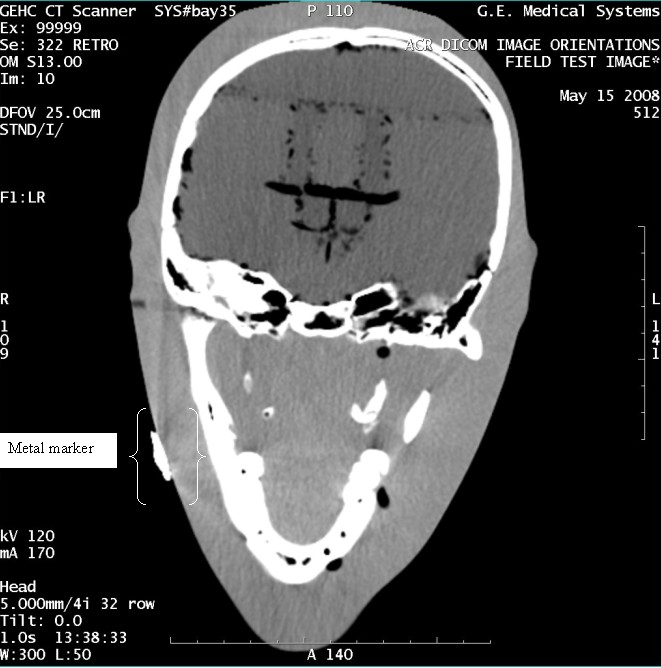

- With the support of the site personnel, examine the images sent

to the Review Station (i.e., 12 series, each with 1 image) and compare

their orientation to the images in this document.

- Each image contains a metal marker on the phantom's right cheek.

- Each image in this document contains a description of the expected

orientation of the metal marker (i.e. to prove Left and Right) as

well as the Posterior and Anterior orientation description.note:

The sample images included in this document use “R”, “L”, “P”, and “A” for “Right”, “Left”, “Posterior” and “Anterior” orientation. The Hospital Review Station may use a different style of annotation. The style used is not relevant to this procedure.

- Each image in this document has sufficient space to store the observed results for up to 4 Review Stations.

- Enter ‘Y’ in the space to indicate the observed result matches the expected.

- Enter ‘N’ in the space to indicate the observed result does not match the expected.

- Enter “NA” in the space if a column is not being used.

- Repeat for each destination.

Figure 6. Exam 99999, Series 322

Figure 7. Exam 99999, Series 328